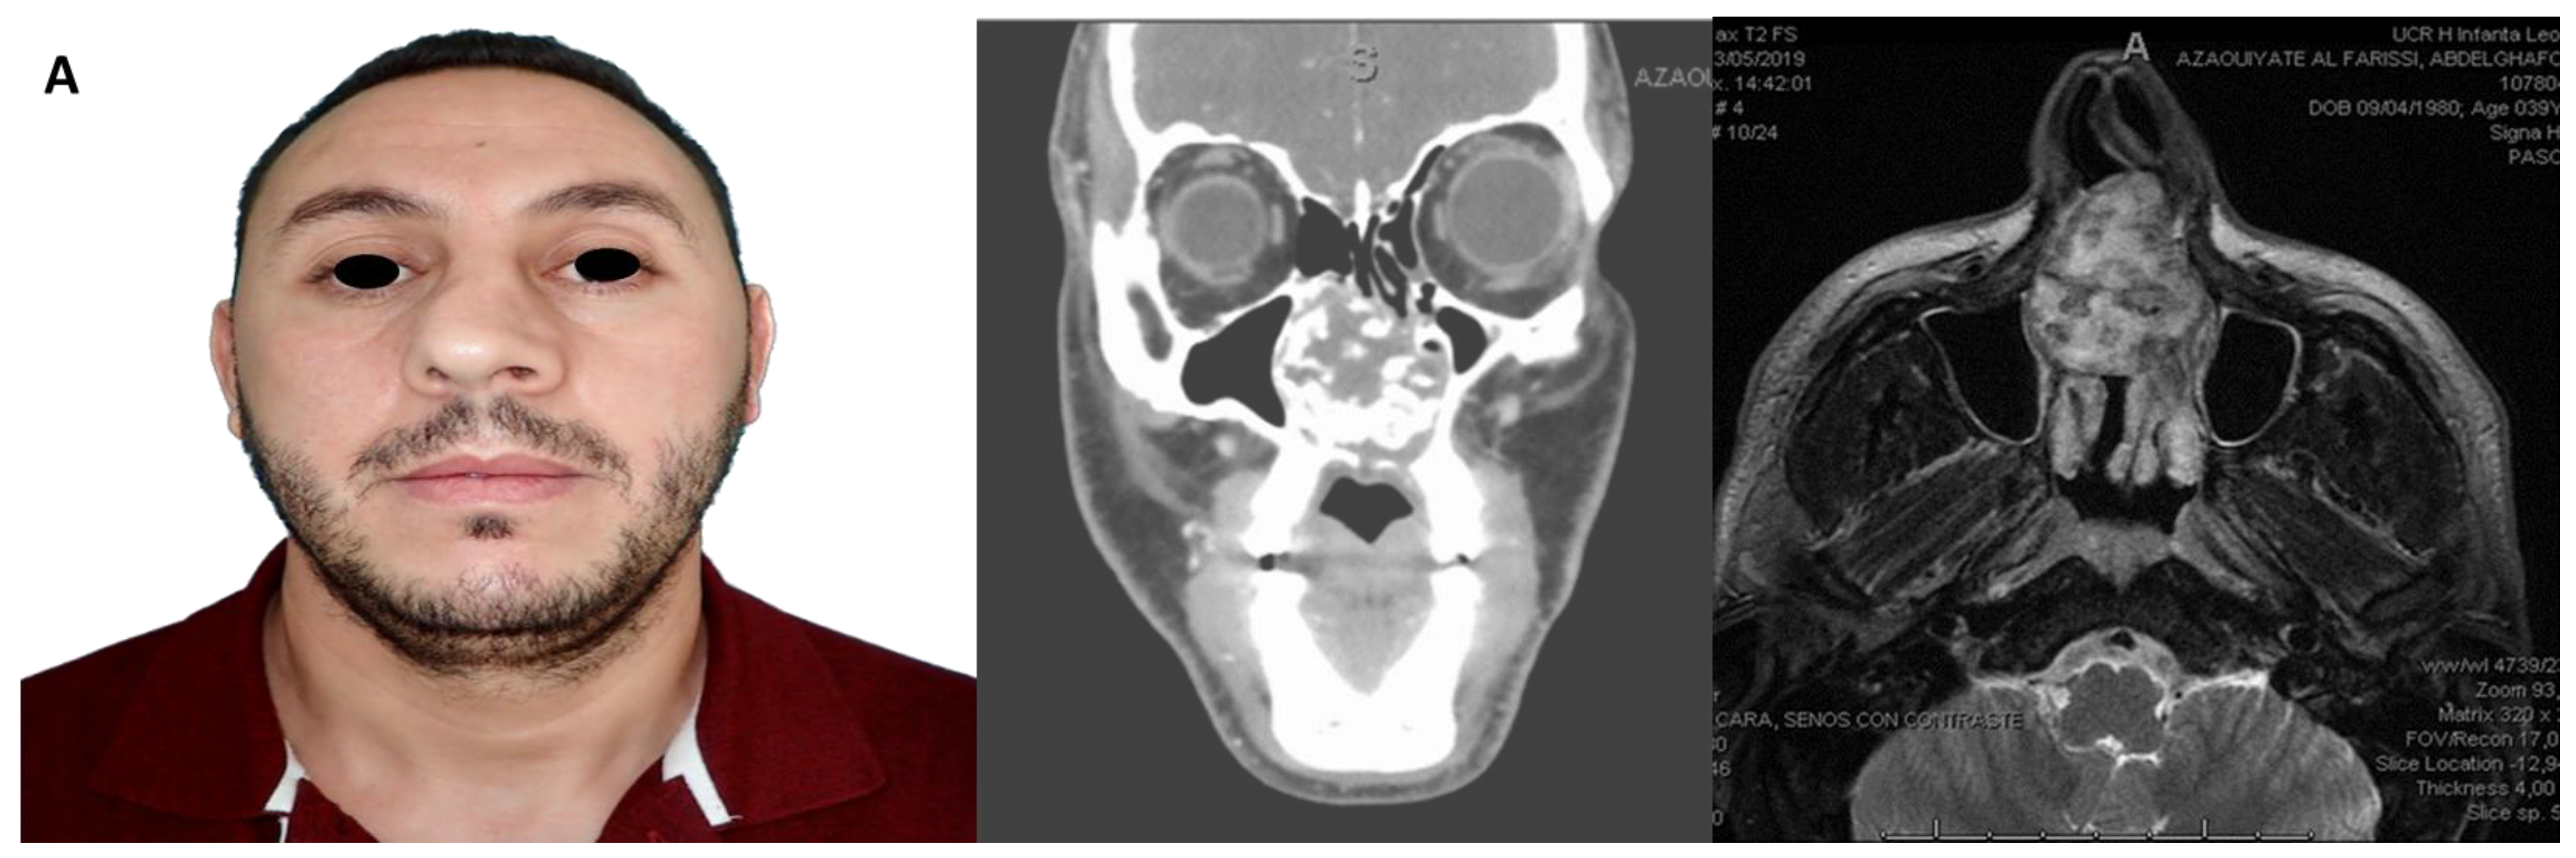

3.2. Anatomic and Oncologic Distribution

| Diagnosis | SCC/Ameloblastoma/Other benign | 18/9/3 | Oral cavity oncologic reconstructions |

| Reconstruction type | Fibula/Iliac/Native | 20/2/8 | Based on surgical notes |

| Radiotherapy | Yes/No | 9 (30%)/21 (70%) | ≥50 Gy in irradiated patients |